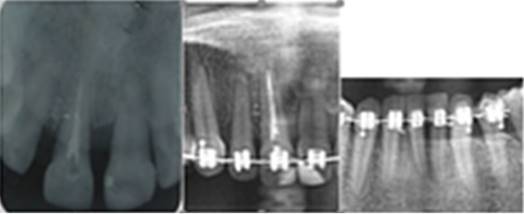

Estudio radiográfico periapical: pérdida ósea horizontal hasta tercio medio a nivel de incisivos superiores. Pérdida ósea ligera en el resto de las arcadas dentarias, ensanchamiento periodontal y pérdida de la cortical alveolar. TPR en 11, con región periapical sin alteraciones visibles

Radiográficamente (Figura 3) se observó reparación ósea con incremento de la densidad ósea y recuperación de la cortical alveolar.